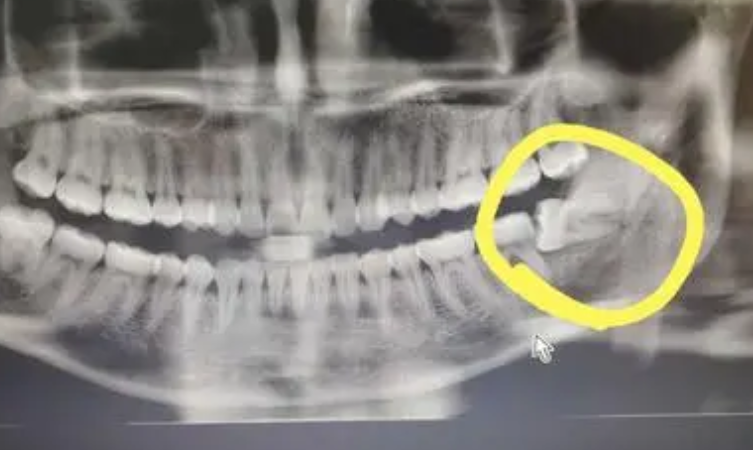

拔智齒之前

我的口腔當(dāng)中左側(cè)下面的智齒經(jīng)常會(huì)導(dǎo)致我牙齦疼痛,后來我才知道,這是因?yàn)檫@個(gè)牙齒有埋伏現(xiàn)象,為了能夠使這顆牙齒帶來的疼痛快點(diǎn)得到消除,我在南方醫(yī)科大學(xué)珠江醫(yī)院的牙科做了拔智齒的手術(shù)。

拔智齒過程中

在拔智齒的時(shí)候,醫(yī)生給我使用了麻藥,所以拔智齒的時(shí)候雖然有點(diǎn)疼痛感,但并不是特別的嚴(yán)重。工作手術(shù)手法比較輕柔,做完之后創(chuàng)口恢復(fù)的也挺快的,不到兩周的時(shí)候就已經(jīng)看上去恢復(fù)如初了,不過醫(yī)生告訴我還需要做好護(hù)理,要在一個(gè)月之后才能夠真的恢復(fù)好。

拔智齒之后

現(xiàn)在我拔完智齒已經(jīng)兩個(gè)多月了,果然沒有了這顆智齒之后,我的牙齒再也沒有出現(xiàn)發(fā)炎疼痛的癥狀,而且口腔的整體健康度都比較好。